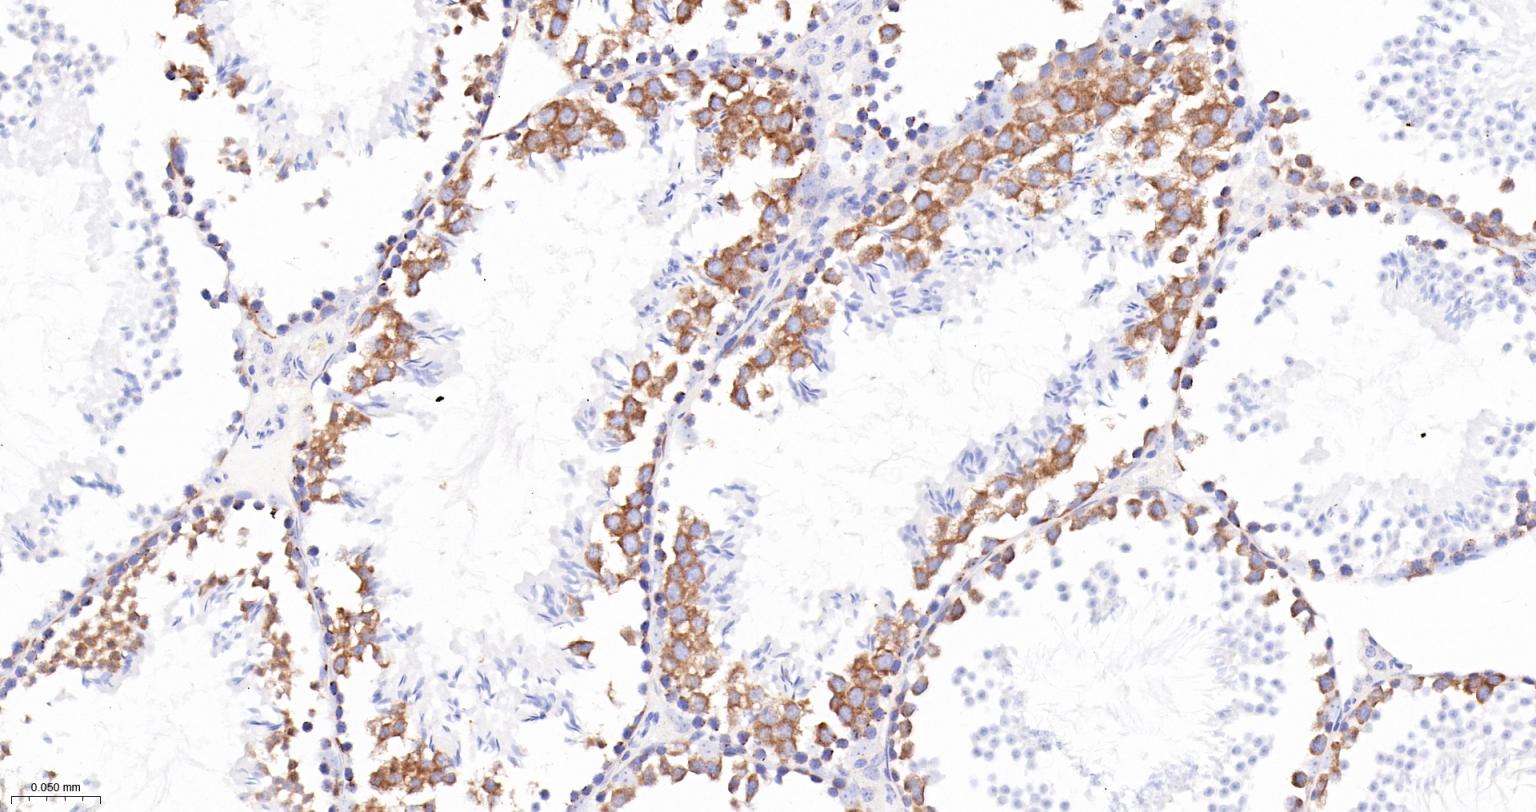

Paraformaldehyde-fixed, paraffin embedded Human Ovarian Cancer; Antigen retrieval by boiling in sodium citrate buffer (pH6.0) for 15 min; The section was incubated with TACC3 Monoclonal Antibody, Unconjugated (bsm-61119R) at 1:200 overnight at 4°C, followed by conjugation to the bs-0295G-HRP and DAB (C-0010) staining.